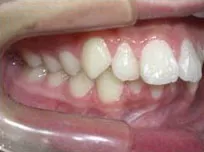

以下、当院で実施した床矯正の症例となります。

症例1

| 治療期間 | 11ヶ月(2021年6月〜2022年5月) |

| 費用 | 495,000円(税込) |

| リスクや副作用 | 成長期が終わった18歳以降に、2期矯正が必要になることがある |